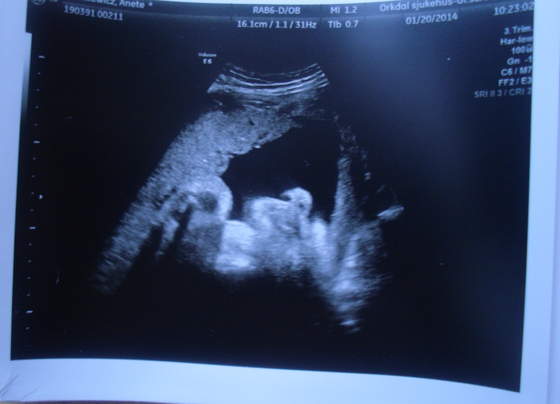

Moja Amelka to całymi dniami fika

i się właśnie zastanawiam kiedy ona śpi? mam nadzieję, że jak się urodzi to będzie spać więcej